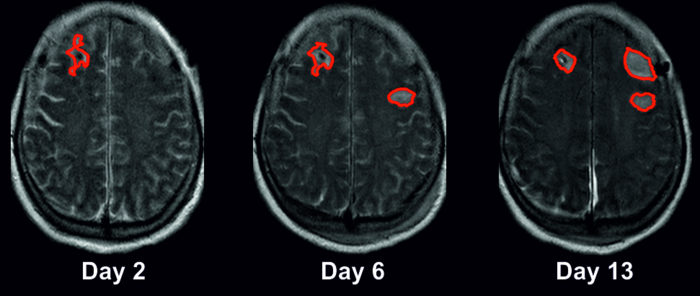

This was the starting point of the current clinical study, which was conducted across five different university hospitals. In order to take accurate measurements of spreading depolarizations, the researchers employed electrocorticography, a procedure used to measure brain activity in neurological intensive care patients. To enable these types of measurements, patients admitted with subarachnoid hemorrhage had electrodes implanted under the dura mater (the brain’s tough outer membrane). The researchers also used imaging technologies such as magnetic resonance imaging (MRI) and computed tomography (CT), analyzing approximately 1,000 brain scans from 180 patients with subarachnoid hemorrhage. The largest clinical study on spreading depolarizations to date revealed that the average patient loses 46 milliliters of brain tissue during the early phase after their brain bleed, i.e., by the time they reach hospital. The average patient then loses a further 36 milliliters of brain tissue during the first two weeks after their hemorrhage, i.e., while in intensive care.